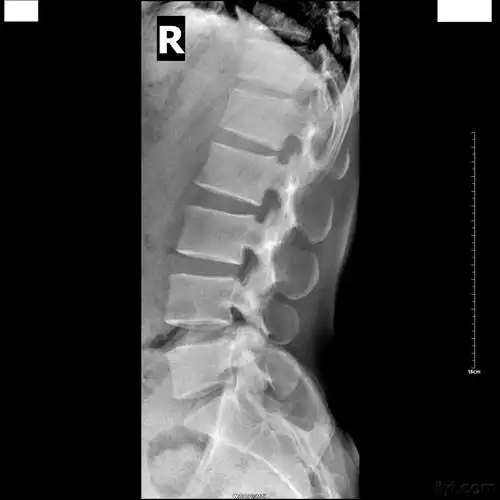

脊柱裂隐性脊柱裂脊膜膨出脊髓脊膜膨出

骶椎隐裂是什么鬼?能治好吗?

今天又有一例s1隐裂

骶椎隐形脊柱裂是怎么回事?有没有图片共享一下?

今天去拍x线,诊断为骶骨隐性裂,而且我问了两个骨科医师,他们看片后

下述图片有骶椎裂吗还是骶管裂畸形

先天性脊柱裂的诊断